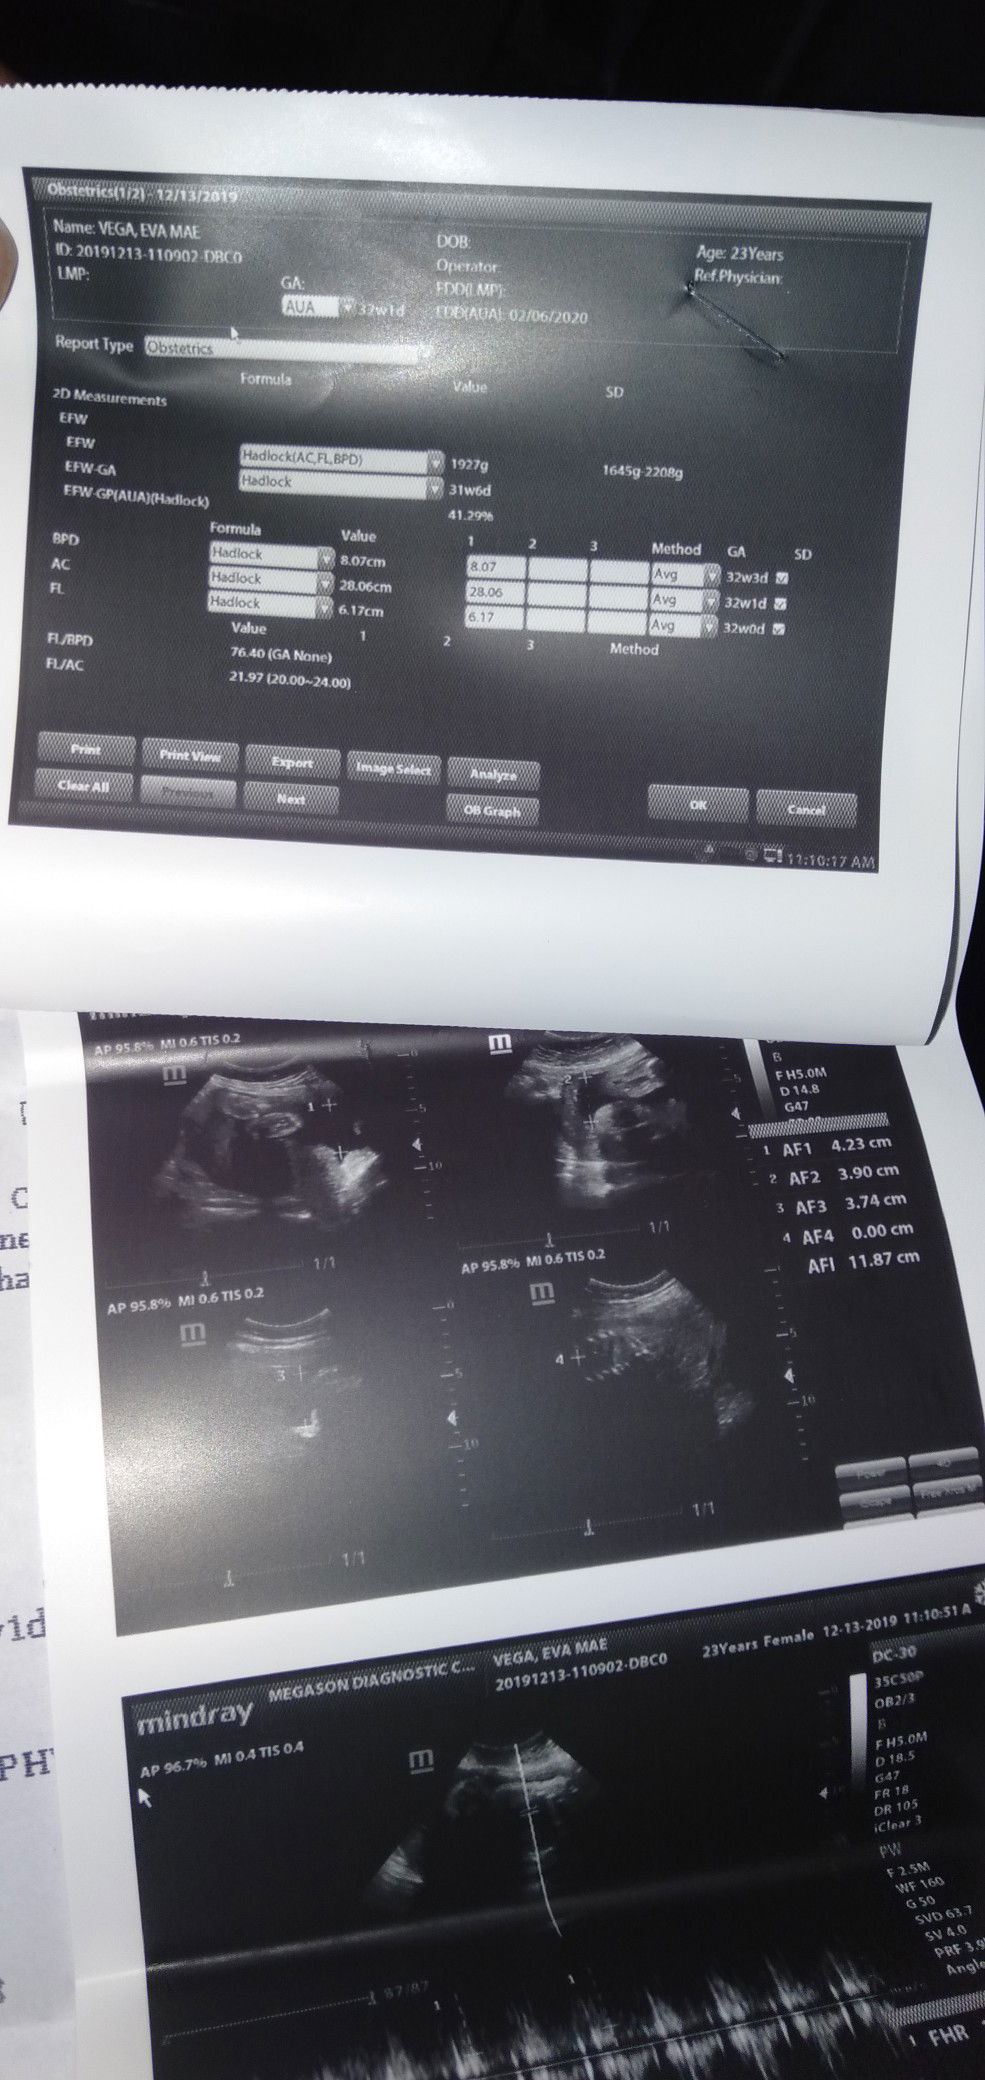

Now i realize hind pla tlga totoo ang sabi sabi,kasi sabi nila pag nangitim kili kili mo at leeg lalaki daw anak mo.but not true ,,kaka ultrasound ko lng ngayun babae po anak ko.kala ko tlga lalaki eh.pru hndi.but thank you lord binigay mo sakin babae ..

agree ako sis kasi ako nangitim talaga lahat sakin at pumangit din ako madaming nagsasabi na lalaki daw ang baby ko pero nung nagpa ultrasound ako ayun at babae si baby kitang kita yung private part nya hahaha 😊 madaming naguyo sa itsura ko turning 8months preggy ako 😊